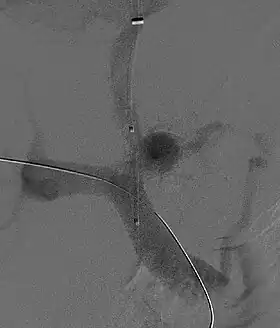

Selective shunts select non-intestinal flow to be shunted to the systemic venous drainage while leaving the intestinal venous drainage to continue to pass through the liver. The most well known of this type is the splenorenal.[34] This connects the splenic vein to the left renal vein thus reducing portal system pressure while minimizing any encephalopathy. In an H-shunt, which could be mesocaval (from the superior mesenteric vein to the inferior vena cava) or could be, portocaval (from the portal vein to the inferior vena cava) a graft, either synthetic or the preferred vein harvested from elsewhere on the patient's body, is connected between the superior mesenteric vein and the inferior vena cava. The size of this shunt will determine how selective it is.[35][36]

With the advent of transjugular intrahepatic portosystemic shunting (TIPS), portosystemic shunts are less performed. TIPS has the advantage of being easier to perform and doesn't disrupt the liver's vascularity.[37]